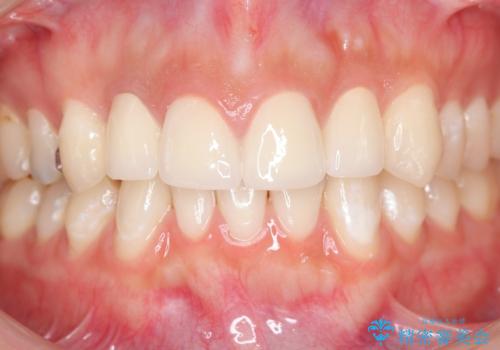

充填物の変色を繰り返す前歯のセラミック治療

充填物や充填物下に再発した虫歯を丁寧に除去し、セラミッククラウンによる審美性の改善、虫歯治療を計画します。

- 52.8万円(ジルコニアクラウン×4・仮歯×4)費用は治療当時の料金となります

レジン修復による充填は、劣化し、色調の変化による審美障害が生じることが多々あります。

ある程度の大きさになった充填物は、劣化の少ないセラミッククラウンにすることで色調の劣化を抑え、審美性を保つことができます。